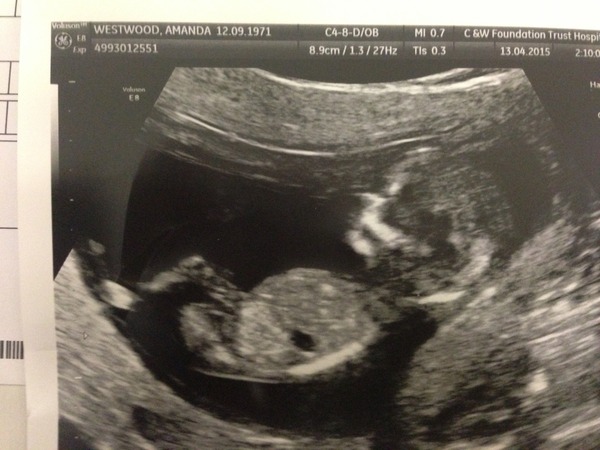

AmandaMae · 13/04/2015 15:50

Hello all. Still struggling with the N and V, but had my NHS 12 week scan today. Measuring 12+5 so ahead of where I thought I was! Will need to wait and get the blood results factored in (same timeline as you, crumbelina) but the nuchal measurement was significantly under the "danger zone" for Downs. Being the oldest on here at the ridiculous age of 43, this is fab news. Not counting my chickens, you understand...

Gorgeous pics, crumbelina and focusfocus! Let me add mine to the gallery.

Wow AmandaMae that is a great scan picture!

Just had to peep at your scan Amanda how cute!

Oo that's a goodun Amanda! It's all suddently getting REAL!

Cool scan amanda the lil baby looks so comfy!

Great pic Amanda! Looks very comfy! And tall!

Amanda what an amazing scan pic you have :) lovely!!!

Gorgeous pic amanda!! And great news on the nuchal measurement.